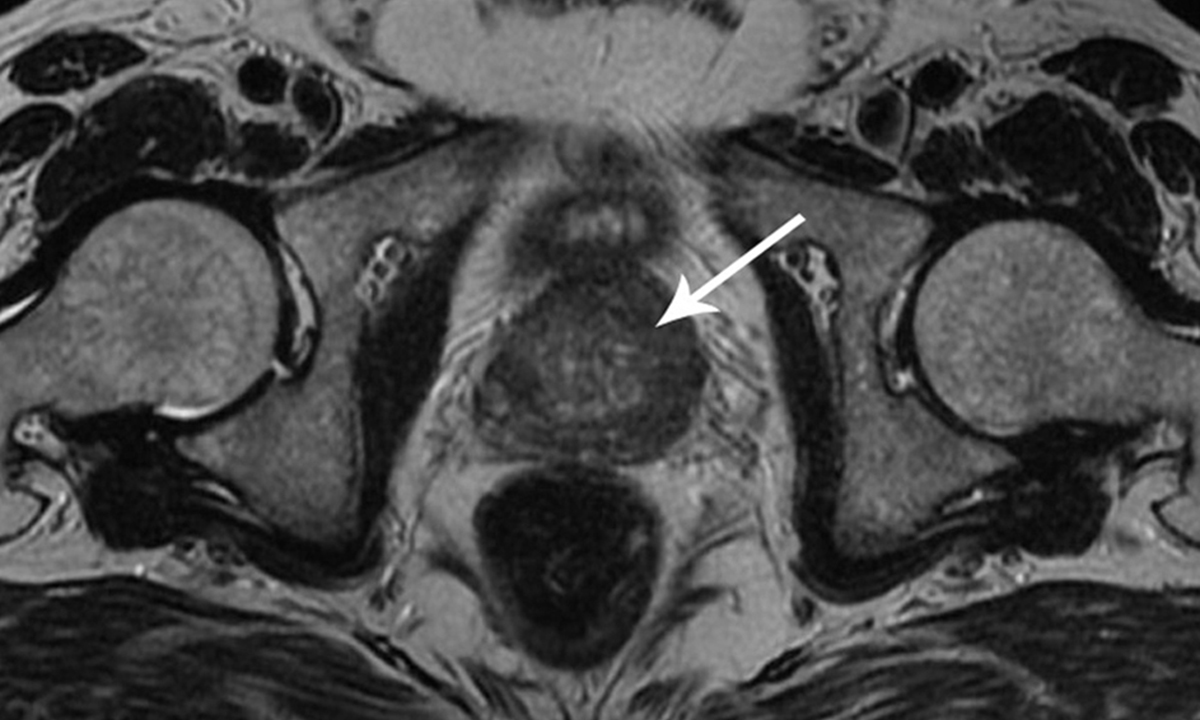

OK, let’s get on with it. Yesterday I had my first treatment for cancer, prostate cancer, that has spread to the bone, to be precise. Today, it doesn’t seem that any side effects have kicked in. Praise God!